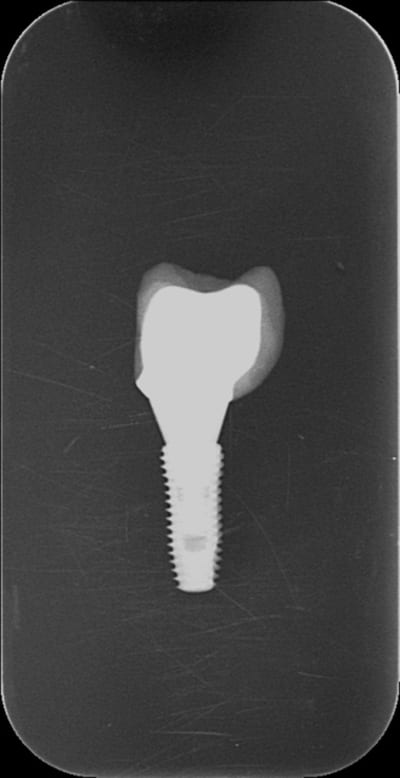

Je ne peux pas expliquer les erreurs des autres, sans avoir vu les radios.

En 3 minutes j'ai pris deux Rx (même tube, même dent même capteur, même distance) : dans un cas le pilier n'est pas vissé à fond (pas bon) dans l'autre cas il l'est (bon), note la distance entre la vis et le fond de l'implant (courte quand la vis est à fond, longue quand elle ne l'est pas ) et le hiatus clairement visible entre la cone de guidage (comme dirait Dr Marcus) et l'intrados de l'implant.

Voilà je t'ai montré, maintenant si je t'en montre 100 et qu'il y en a 10 de pas bien vissé dedans,je pense que (si les clichés sont bons et ta vue correcte) tu les retrouveras :-)

Je précise que c'est LA SEULE façon de ne pas bien le positionner, après l'autre erreur est de ne pas visser à fond ..